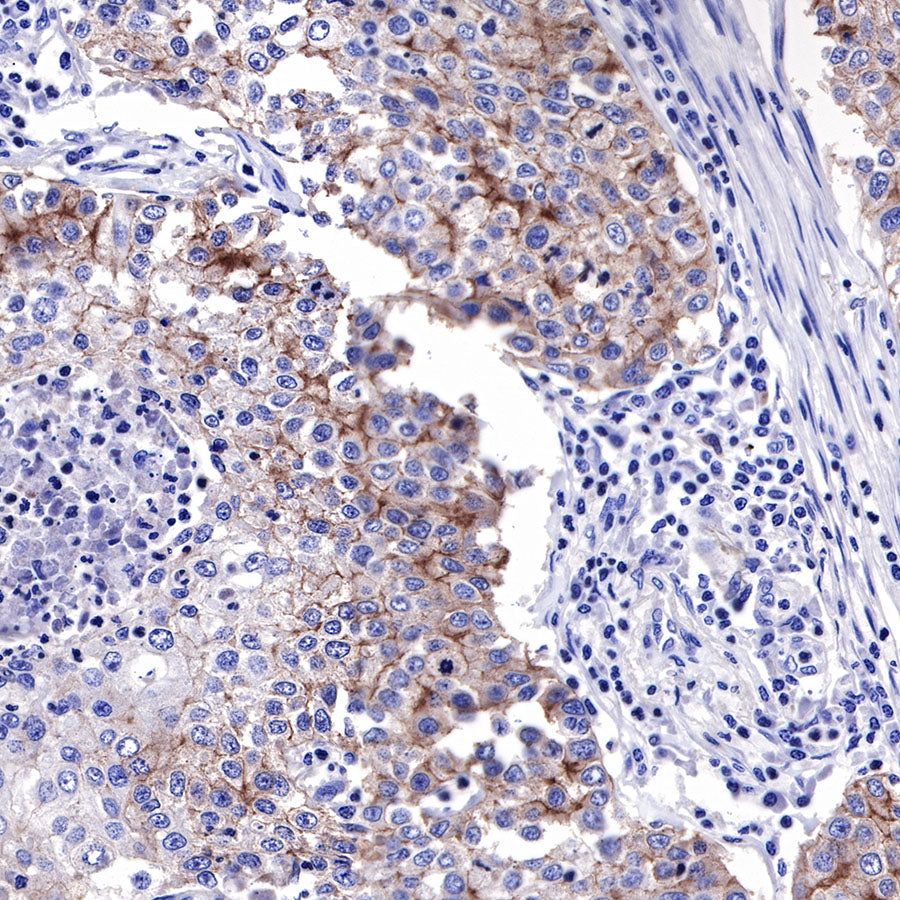

IHC shows positive staining in paraffin-embedded human endometrial cancer. Anti-EGFR antibody was used at 1/2000 dilution, followed by a HRP Polymer for Mouse & Rabbit IgG (ready to use). Counterstained with hematoxylin. Heat mediated antigen retrieval with Tris/EDTA buffer pH9.0 was performed before commencing with IHC staining protocol.

IHC shows positive staining in paraffin-embedded human cervical squamous cell carcinoma. Anti-EGFR antibody was used at 1/2000 dilution, followed by a HRP Polymer for Mouse & Rabbit IgG (ready to use). Counterstained with hematoxylin. Heat mediated antigen retrieval with Tris/EDTA buffer pH9.0 was performed before commencing with IHC staining protocol.